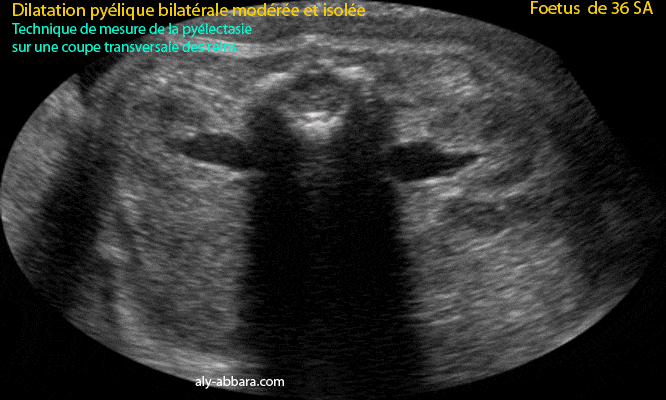

Dilatation pyélique bilatérale (pyélectasie) et modérée

Fœtus âgé de 36 SA

Coupe échographique transverse du tronc fœtal au niveau lombaire, passant par les deux reins et montrant l'aspect ultrasonore de la dilatation pyélique bilatérale modérée. Puis l'image montre la technique de la mesure de la pyélectasie, il s'agit de calculer le diamètre maximal antéro-postérieure (et non le transverse) du bassinet.

Dans le cas présent, il s'agit d'une pyélectasie bilatérale modérée et isolée.